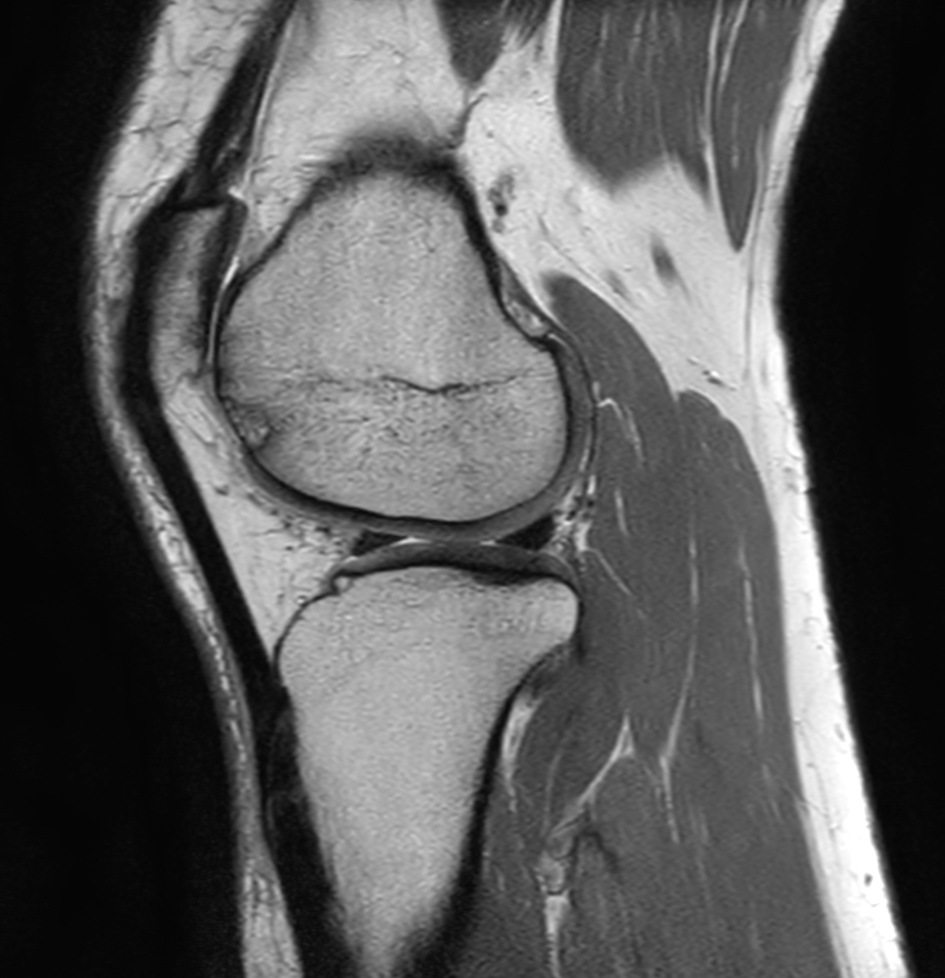

Sagittal PDw TSE